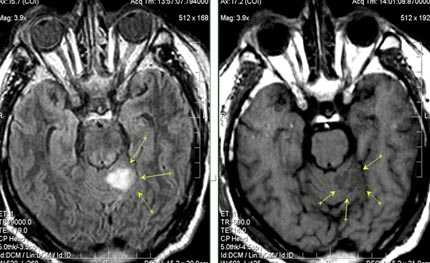

При поражениях крупных (магистральных) артерий развиваются обширные, территориальные, инсульты соответственно зоне кровоснабжения пораженного сосуда. Вследствие повреждения мелких артерий формируются лакунарные инсульты с мелкими очагами поражения.

Бассейн кровоснабжения левой верхней мозжечковой артерии, острая стадия НМК.

Зона подострого ишемического НМК, в бассейне правой средней мозговой артерии. В режиме Т1 визуализируется симтом «вуалирования»- изоинтенсивность МР-сигнала.

Подострая стадия ишемического НМК. При внутривенном контрастировании определяется накопления КВ в бороздах на уровне зоны ишемии (гиральный тип усиления).

Зона хронического ишемического НМК, в бассейне левой задней мозговой артерии.

Ишемическое ОНМК, ствол мозга (подострый период)